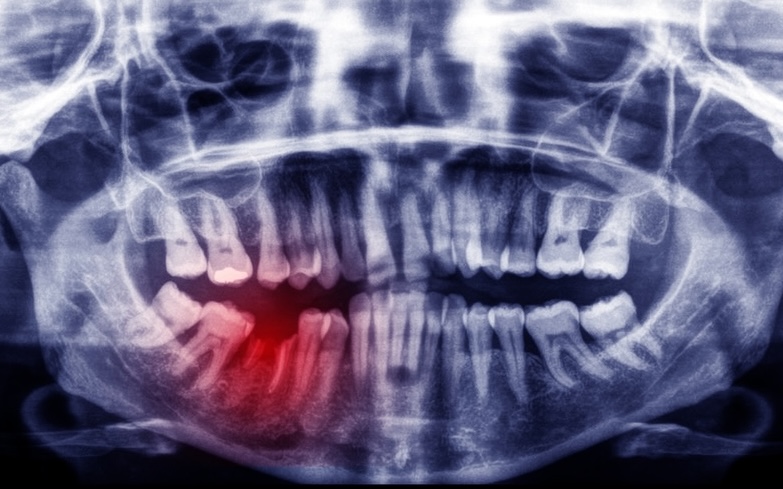

This is the most severe type of chipped tooth. It often happens from a fall, car accident, or sports injury. The tooth may be shifted out of place, fractured to the root, or extremely painful.

Get stabilized. Doctors will take X-rays and address any urgent injuries, like broken facial bones.

After you’re stabilized, we’ll assess your tooth and develop a plan. Depending on the damage, this may include splinting, root canal treatment, or in some cases, removing the tooth and replacing it with an implant and crown.